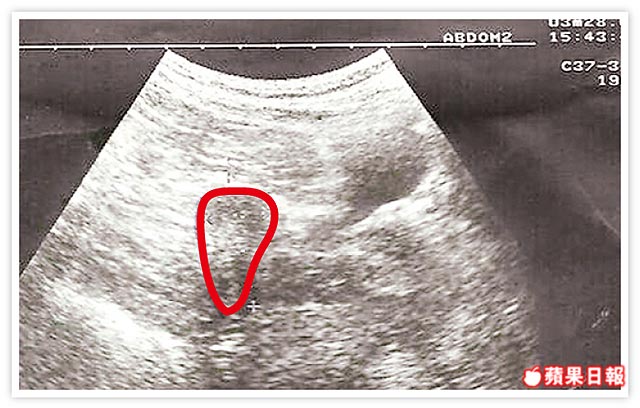

罕見!子宮內外複合受孕!她​ 輸卵管化膿 ​手術後在博元婦產科​ 做試管嬰兒     ​竟然​ 兩邊輸卵管  ​各​ 外孕,子宮有一個健康的寶寶,生下來3000公克, &nb...